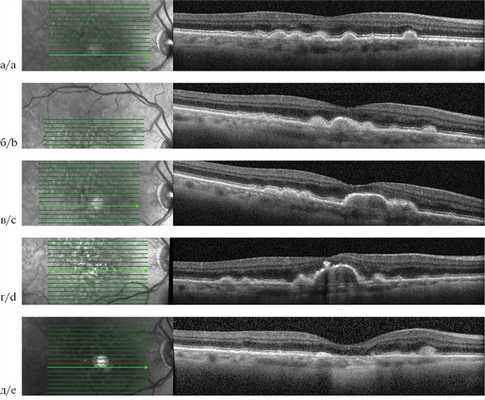

При оптической когерентной томографии (ОКТ) визуализируется ячеистая, куполообразная структура с волнистой поверхностью и подлежащей зоной гомогенного гиперрефлективного сигнала средней интенсивности. Участки отложения пигмента видны как интраретинальный гиперрефлективный материал высокой интенсивности. Над друзеноидной ОРПЭС можно обнаружить гиперрефлективную линию — ретинальный пигментный эпителий (рис. 1).

Рис. 1. Оптическая когерентная томограмма пациента с друзеноидной отслойкой ретинального пигментного эпителия сетчатки.

Начальный этап развития ОРПЭС характеризуется аккумуляцией друзеноидного материала между РПЭ и мембраной Бруха. Напряжение кислорода снижается на 30—50% у вершины в зависимости от роста друзеноидной ОРПЭС. Клетки РПЭ, лежащие на верхушке друзы, максимально удалены от хориокапилляров и могут мигрировать в поисках кислорода из капилляров сетчатки. Оставшиеся клетки РПЭ подвержены апоптозу, разрушению с переходом органелл клетки в состав друз [8]. Последующая фаза — регрессия, протекает с прогрессированием атрофии наружных слоев сетчатки по мере уменьшения количества клеток РПЭ на поверхности ОРПЭС. Процесс образования друзеноидного материала заканчивается, происходит «самоочищение» последнего, объем ОРПЭС уменьшается, и в конечном итоге наблюдается коллапс друзеноидной ОРПЭС, на месте которой регистрируется зона полной атрофии РПЭ и наружных слоев сетчатки (географическая атрофия). По мнению J. Sarks и соавторов, по мере увеличения как мягких сливных друз, так и друзеноидной ОРПЭС материал внутри них распадается и становится более тонким по своей природе, что приводит к более быстрому коллапсу друзы и развитию географической атрофии [9]. На ОКТ при этом можно наблюдать негомогенный характер друзеноидного материала с появлением гипорефлективных участков. Даже до явного развития географической атрофии ОРПЭС приводит к дисфункции фоторецепторов и последующей наружной атрофии сетчатки. Для друзеноидных ОРПЭС, выявленных на раннем этапе развития, характерна высокая острота зрения. Развитие наружной атрофии сетчатки в процессе существования ОРПЭС может объяснять потерю 15 и более букв в 26% случаев в отсутствие прогрессирования до поздней стадии ВМД (по классификации AREDS). При офтальмоскопии обнаружено, что при развитии гипопигментации риск снижения остроты зрения удваивается [7, 9] (рис. 2).

Рис. 2. Оптическая когерентная томограмма пациента с возрастной макулярной дегенерацией.

Жизненный цикл друзеноидной отслойки ретинального пигментного эпителия сетчатки от мягких друз до географической атрофии: а — 2013 г.; б — 2014 г.; в — 2015 г.; г — 2017 г.; д — 2018 г.